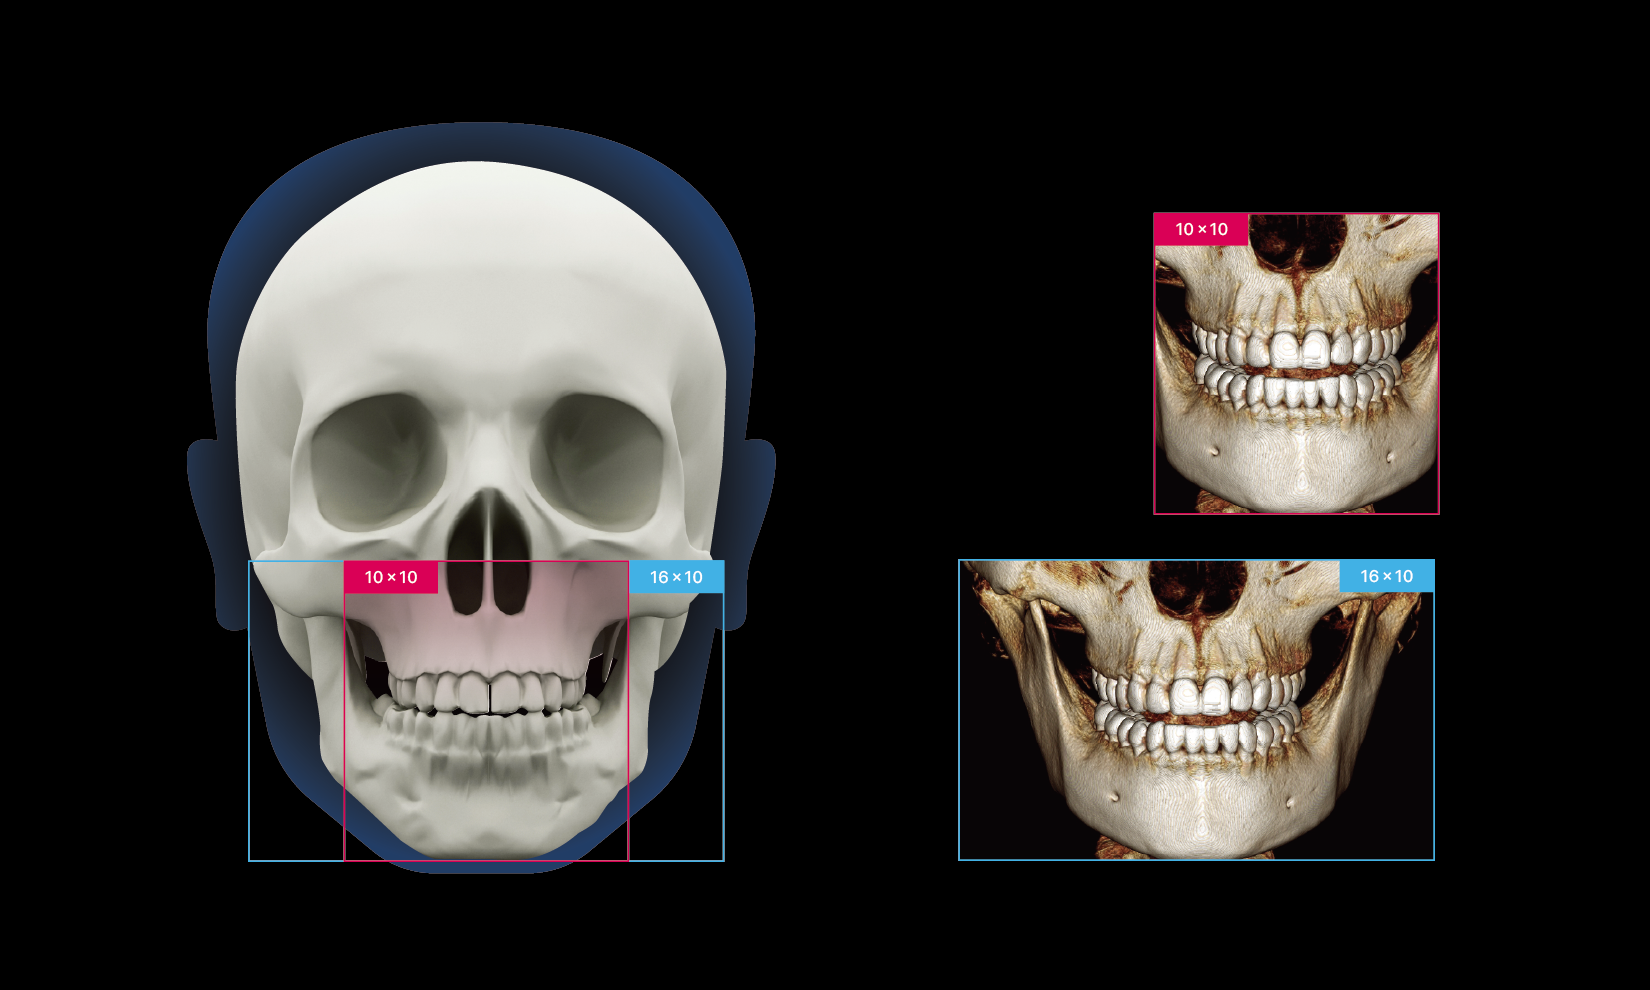

The expanded 16×10 FOV of RAYQuantum captures more details in a single scan, enabling precise diagnostics and comprehensive treatment planning. With high-resolution imaging and fast reconstruction times, it enhances clinical reliability and improves workflow efficiency, contributing to better patient care and treatment outcomes.

The expanded 16×10 FOV of RAYQuantum captures more details in a single scan, enabling precise diagnostics and comprehensive treatment planning. With high-resolution imaging and fast reconstruction times, it enhances clinical reliability and improves workflow efficiency, contributing to better patient care and treatment outcomes.

RAYQuantum allows for quick and easy selection of the scan area through predefined FOV options, supporting a wide range of dental procedures, including implant planning, orthodontics, complex impactions, bilateral TMJ, sinus and airway analysis.

Utilization in a wide clinical range with an extended FOV

Essential coverage for confident diagnostics

RAYQuantum’s expanded 16×10 Field of View ensures clear capture of essential anatomical areas across various diagnostic needs.

Utilization in a wide clinical range with an extended FOV

Essential coverage for confident diagnostics

RAYQuantum’s expanded 16×10 Field of View ensures clear capture of essential anatomical areas across various diagnostic needs.